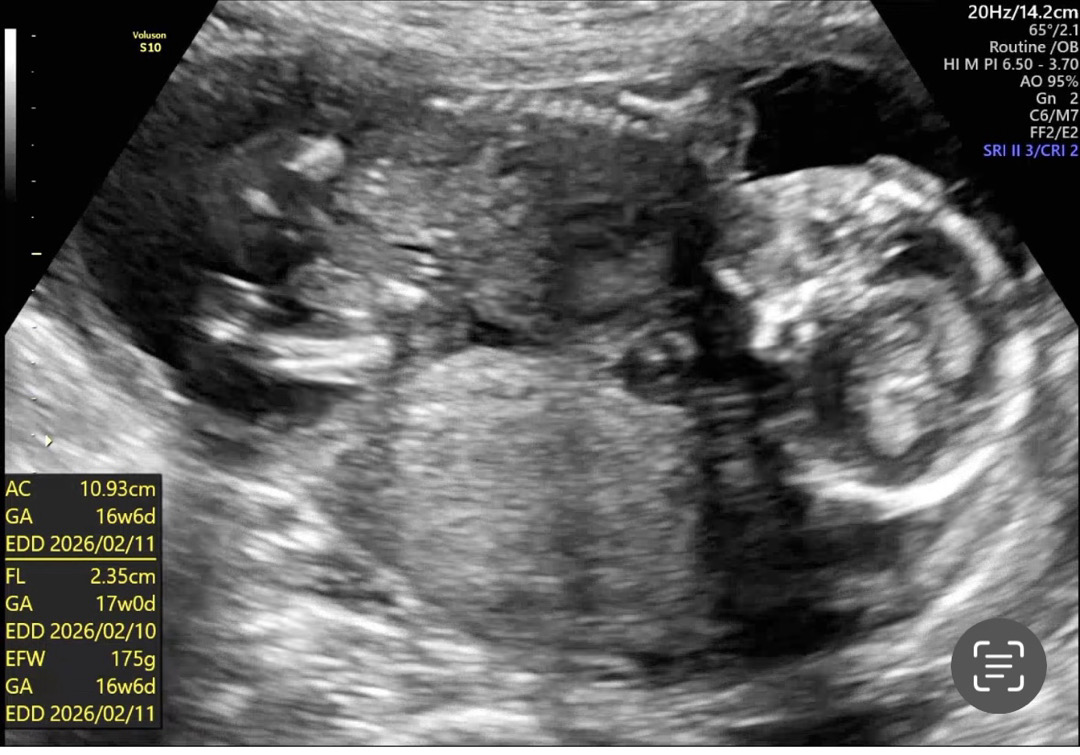

아기가 가부좌자세를 틀었는지 안보여줘요..

15-16주 되면 보인다던데 저희는 17주째 안보여주고 있어요.. 혹시 보이시나요 고수님들..도와주세요